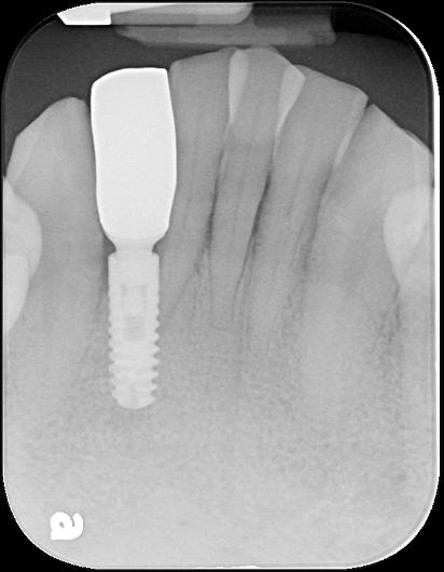

本病患為嚴重蛀牙,導致牙齒斷裂,經評估,骨頭良好,因此可拔牙後立即植牙,減少等待時間,待植體癒合後,再進行膺復處置

1)立即植牙

拔牙、立即植牙、補骨